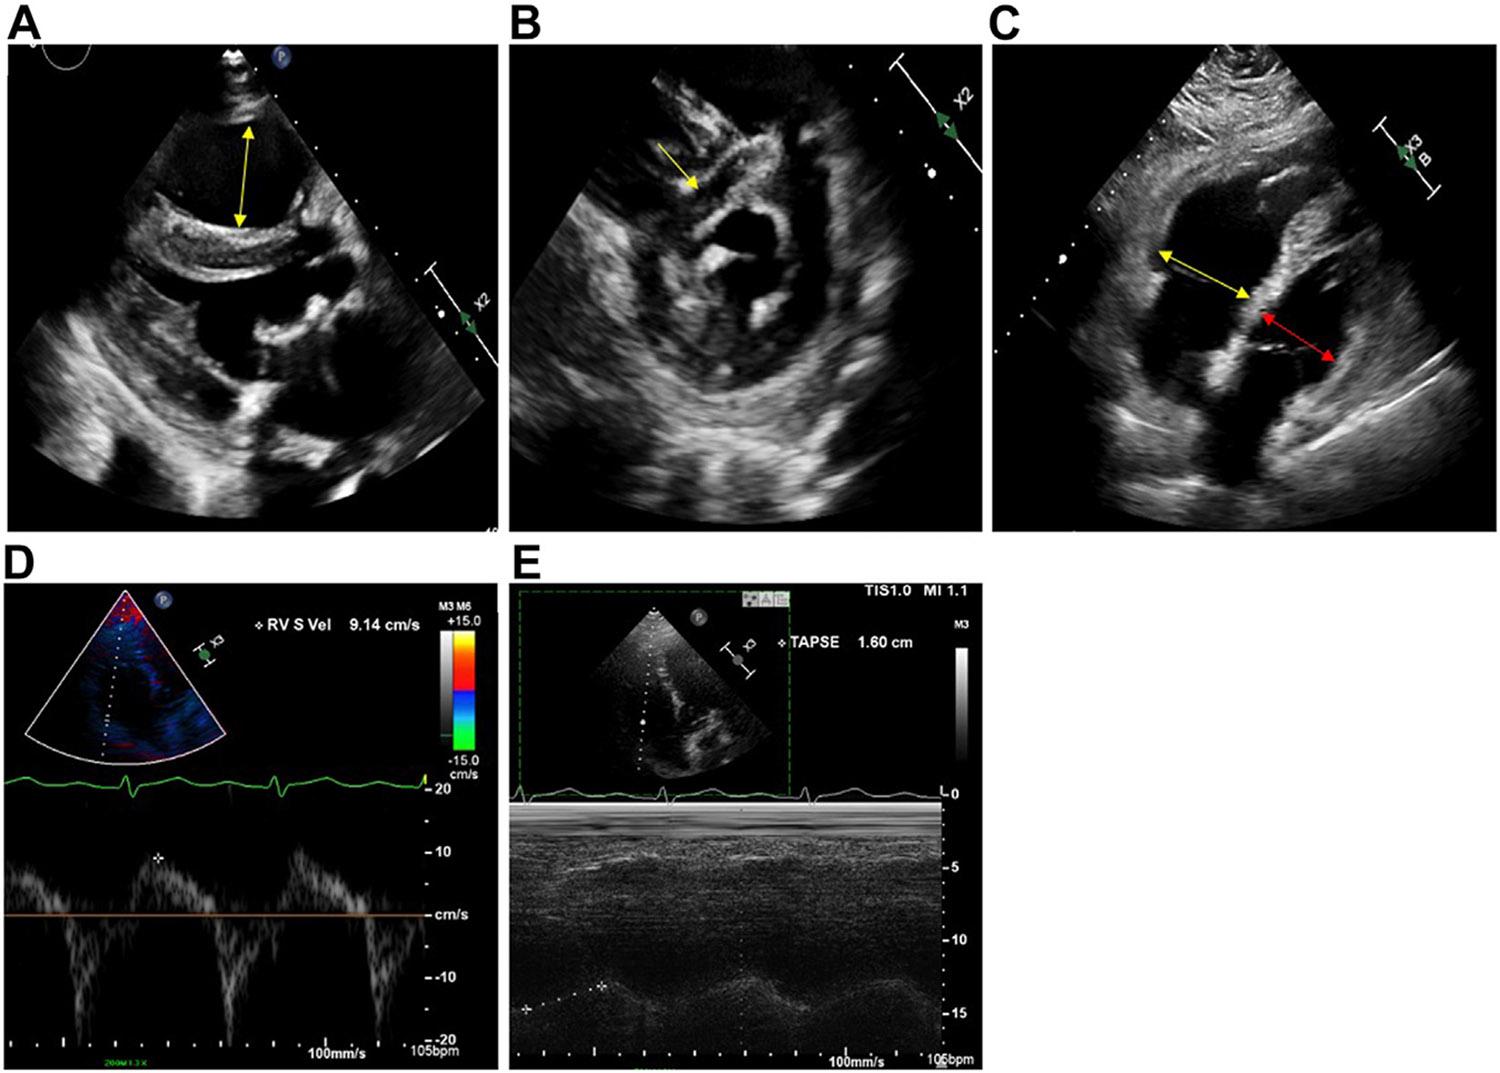

Pulmonary embolism (PE) is a common cardiovascular disease diagnosis in emergency departments that can be associated with significant morbidity and mortality. One of the first steps after diagnosing PE is to risk stratify for adverse outcomes using risk scores such as PE Severity Index and European Society of Cardiology risk scheme. While intermediate- and high-risk PE patients should be admitted to the hospital, there is increasing evidence to support early discharge and home-based anticoagulation therapy for low-risk patients. The Hestia criteria encompass many of the clinicians' considerations for who may be suitable for early discharge, considering both medical and social factors. Additionally, professional guidelines have provided algorithms on determining which low-risk patients may be suitable. Despite this, low-risk acute PE patients are still often admitted for inpatient treatment. In this review, we present a case-based approach on how to risk stratify and evaluate patients who may be good candidates for early discharge and home therapy.

肺栓塞(PE)是急诊科常见的心血管疾病诊断,可导致严重的发病率和死亡率。PE 诊断后的第一步是使用风险评分(如 PE 严重程度指数和欧洲心脏病学会风险方案)对不良结局进行风险分层。虽然中高危 PE 患者应住院治疗,但越来越多的证据支持对低危患者进行早期出院和家庭为基础的抗凝治疗。Hestia 标准考虑了许多医生认为适合早期出院的因素,包括医疗和社会因素。此外,专业指南还提供了确定哪些低危患者可能适合的算法。尽管如此,低危急性 PE 患者仍经常住院接受治疗。在这篇综述中,我们提出了一种基于病例的方法,用于对可能适合早期出院和家庭治疗的患者进行风险分层和评估。